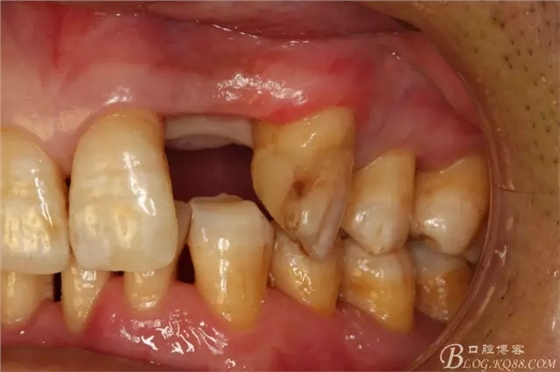

圖3.術(shù)前口內(nèi)照片:正面觀閉口位

圖4.左側(cè)側(cè)面觀,22間隙正常,23近中輕度扭轉(zhuǎn)

圖5.腭側(cè)觀:牙槽嵴豐滿度尚可。